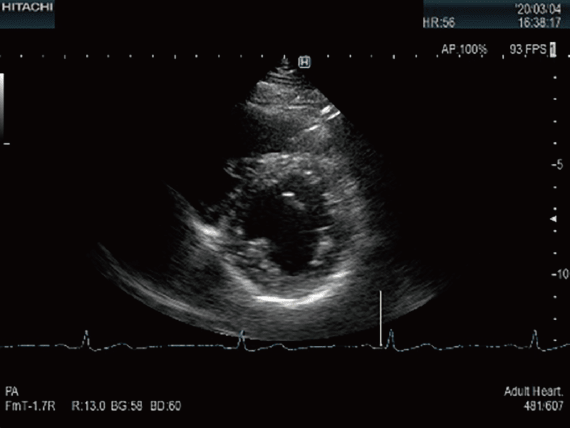

心臓超音波検査

胸部より超音波を照射し,動いている心臓の内部構造を描出し,心臓の動きを動画として観察する検査です。心臓弁膜症や虚血性心疾患,心筋症などの診断に用いられます。治療方法の選択や治療効果の判定,手術時期の決定などに役立ちます。